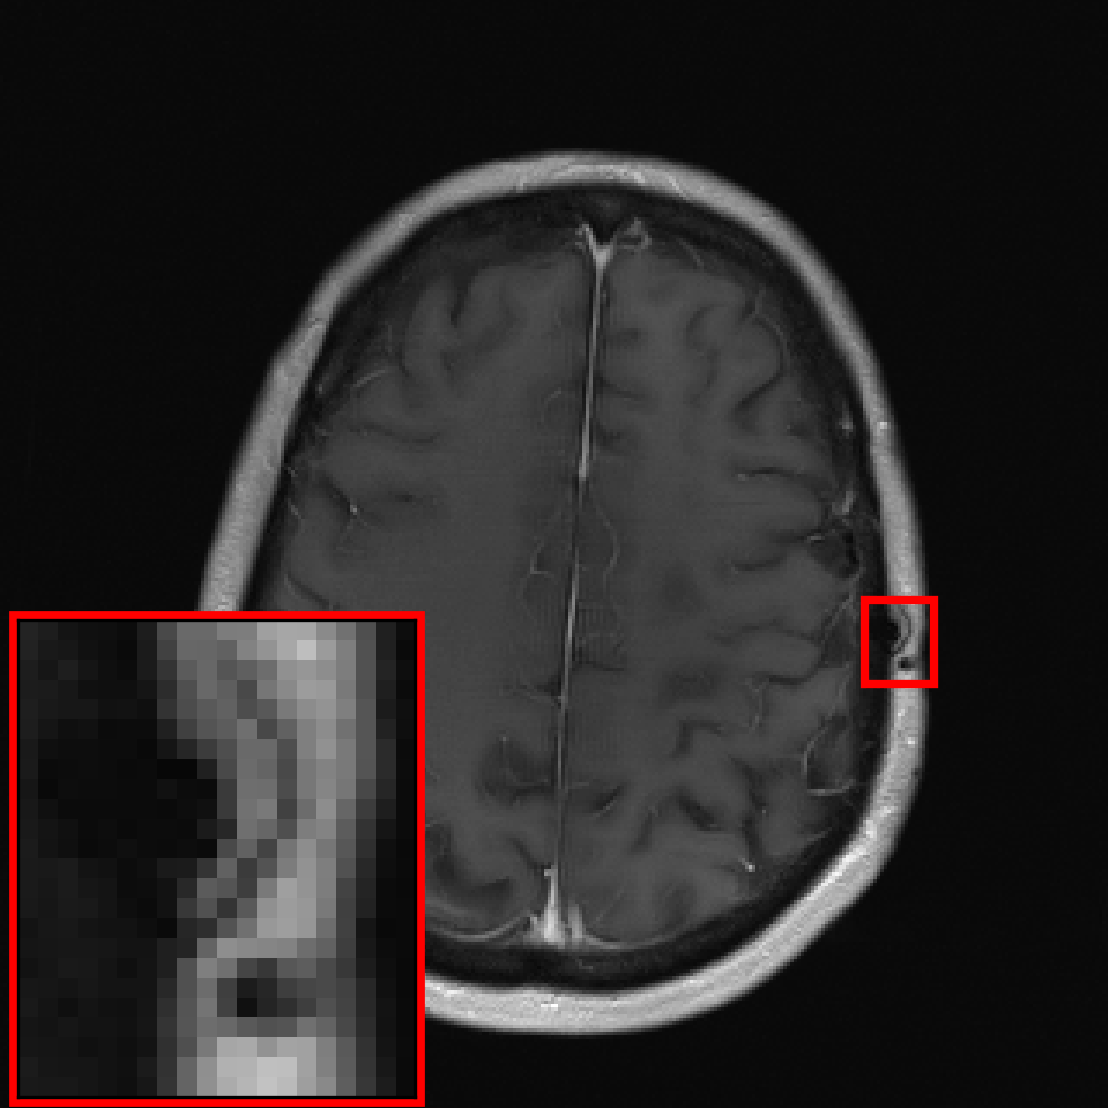

![[Uncaptioned image]](extracted/5298803/figs/pathology/lacunar_infarct_out_varnet.png)

![[Uncaptioned image]](extracted/5298803/figs/pathology/mass_out_varnet.png)

![[Uncaptioned image]](extracted/5298803/figs/pathology/lacunar_infarct_out_varnet_bl.png)

![[Uncaptioned image]](extracted/5298803/figs/pathology/mass_out_varnet_bl.png)

![[Uncaptioned image]](extracted/5298803/figs/pathology/lacunar_infarct_ref.png)

![[Uncaptioned image]](extracted/5298803/figs/pathology/mass_ref.png)

In this section, we investigate the distribution shift from healthy to non-healthy subjects by measuring how well models reconstruct images containing a pathology if no pathologies are contained in the training set. We find that models trained on fastMRI data without pathologies reconstruct fastMRI data with pathologies equally well as the same models trained on fastMRI data with pathologies.

We see that the models trained on show essentially the same performance (SSIM) as models trained on regardless of pathology size. The results indicate that models trained on images without pathologies can reconstruct pathologies as accurately as models trained on images with pathologies. This is further illustrated in Figure 6 (and Figure 16), where we show reconstructions given by the VarNet of images with a pathology: the model recovers the pathology well even though no pathologies are in the training set. Figure 14 in the appendix provides a more nuanced evaluation of the SSIM values for VarNet.